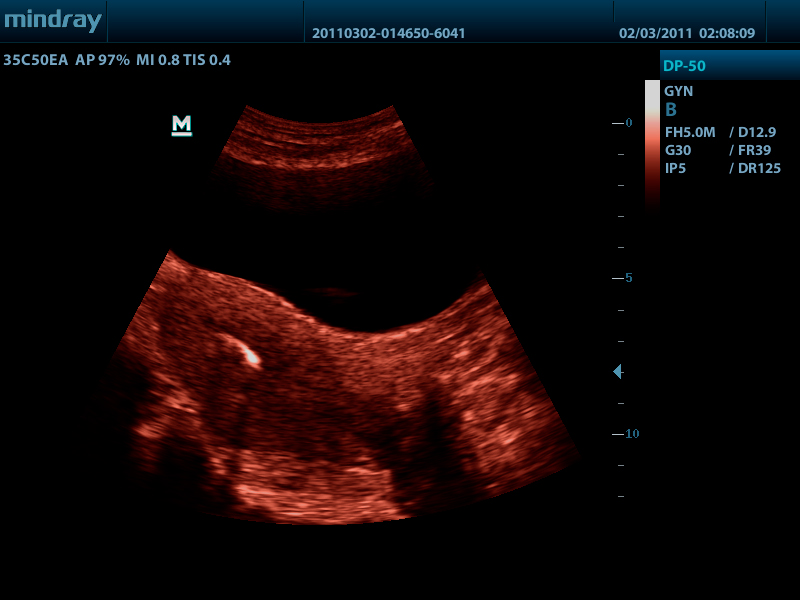

- Псевдоокрашивание

- Конвексный датчик 35C50EA, 1.7 - 6.0 МГц, радиус кривизны 50 мм